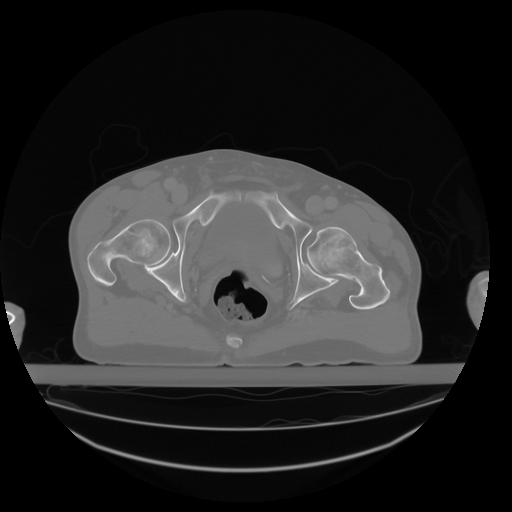

27 CUERPO,CE,Axial,3.0,CUERPO,,